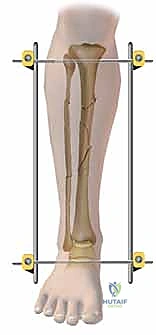

لفهم أهمية التثبيت الخارجي، يجب أولاً فهم طبيعة الساق البشرية. يتكون الساق من عظمتين:

1. عظم الظنبوب (Tibia): وهو العظم الأكبر والأقوى، ويحمل الغالبية العظمى من وزن الجسم.

2. عظم الشظية (Fibula): عظم رفيع يقع على الجانب الخارجي للساق، ويفيد في استقرار الكاحل وتثبيت العضلات.

هنا تبرز براعة هذا الإجراء. يتم إدخال دبابيس معدنية (Pins) في العظم السليم فوق وتحت منطقة الكسر، ثم تُوصل هذه الدبابيس بإطار معدني خارجي (Frame) خارج الجلد.

3. إدخال الدبابيس (Pin Placement)

باستخدام جهاز الأشعة السينية المتحرك داخل غرفة العمليات (C-arm)، يقوم الدكتور هطيف بتحديد الأماكن الآمنة (Safe Corridors) لإدخال الدبابيس المعدنية (Schanz pins). هذه الأماكن يتم اختيارها بدقة متناهية لتجنب إصابة الأعصاب أو الأوعية الدموية الحيوية في الساق. يتم عمل شقوق صغيرة جداً في الجلد وإدخال الدبابيس في العظم السليم فوق وتحت الكسر.

5. تركيب الإطار الخارجي (Frame Assembly)

بمجرد أن تصبح العظام في الوضع الصحيح، يتم توصيل الدبابيس البارزة من الجلد بقضبان معدنية (Rods) أو إطار دائري باستخدام مشابك (Clamps) خاصة. يتم إحكام ربط هذه المشابك لتثبيت العظام بقوة ومنعها من الحركة تماماً.